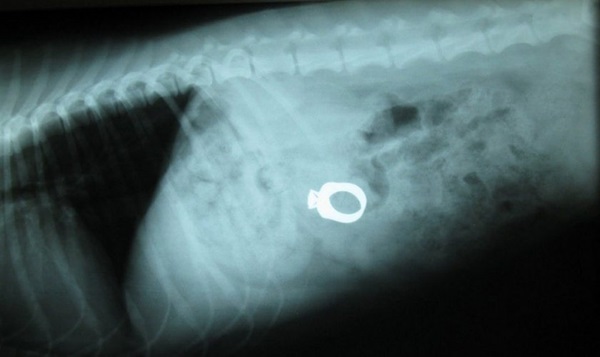

Діагностика включає в себе загальний і біохімічний аналіз крові, ультразвукове дослідження черевної порожнини та рентгенографічне дослідження (за необхідності з контрастом).

Є рентгеноконтрастним предметом. Розташування його в нехарактерному анатомо-топографічному місці підтверджуватиме діагноз.

Метал також є рентгеноконтрастним предметом із характерною впізнаваною формою.